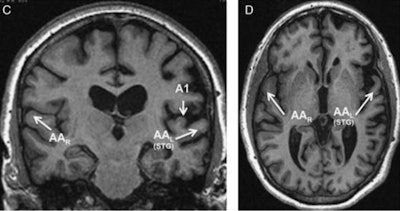

Through MRI, they found the deficiencies were centered in the superior temporal gyrus of the brain's left hemisphere, which is associated with auditory function.